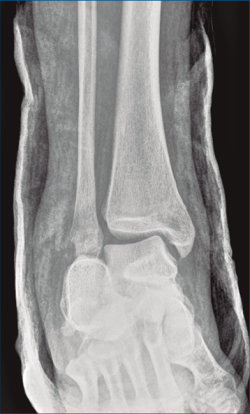

Figura 8. Radiografía anteroposterior de tobillo, inclinación lateral del astrágalo, ocupación del espacio subperoneo, fractura maléolo peroneo y apertura de sindesmosis.

A su llegada a urgencias, se inmovilizó con férula posterior de yeso tras no conseguirse la reducción cerrada (Figuras 7 y 8). Debido a la patología asociada, subsidiaria de tratamiento quirúrgico de urgencias (artrodesis de L2 a L4 con tornillos transpediculares, por parte de neurocirugía), se decide demorar eñ tratamiento definitivo de la fractura luxación de calcáneo 2 semanas, hasta conseguir una mejoría en el estado de las partes blandas.